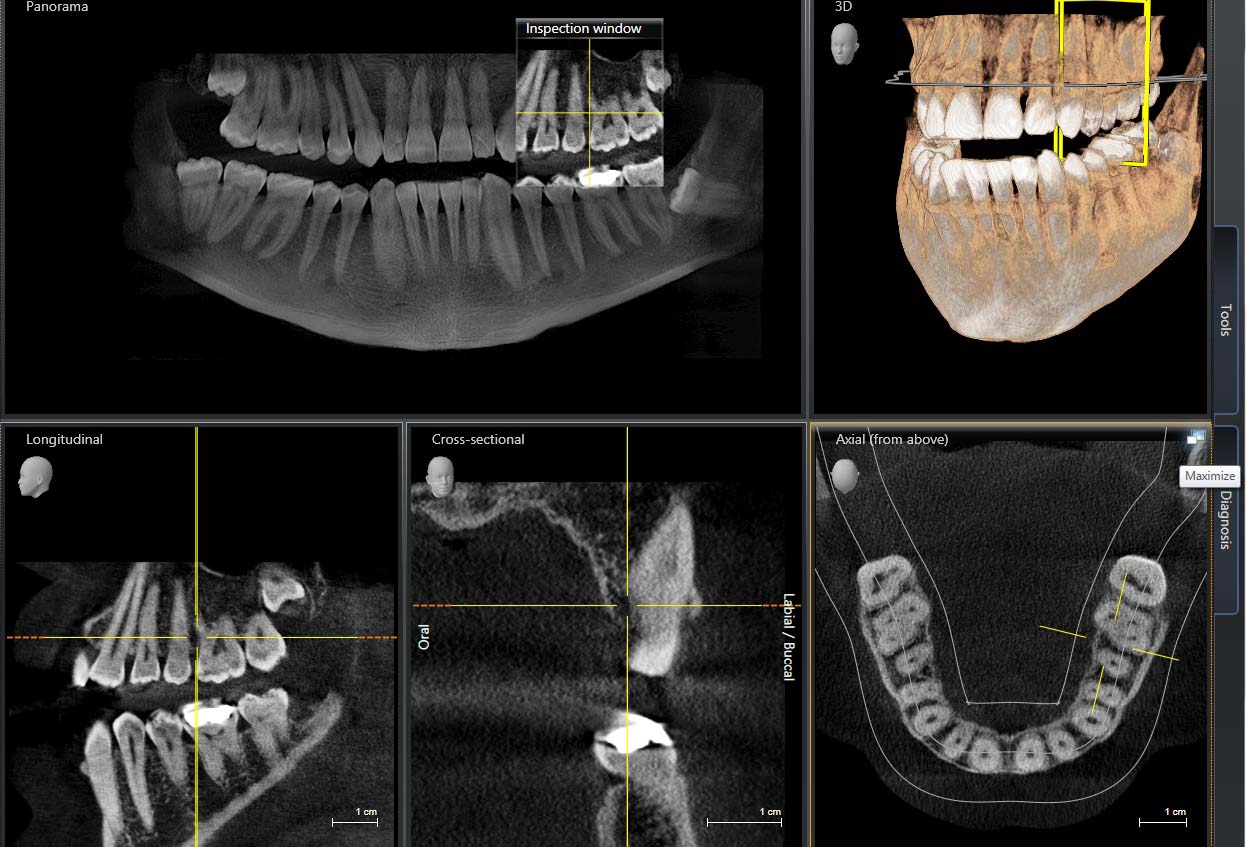

Кт зуба рядом

Кт зуба рядом 109 фотографий